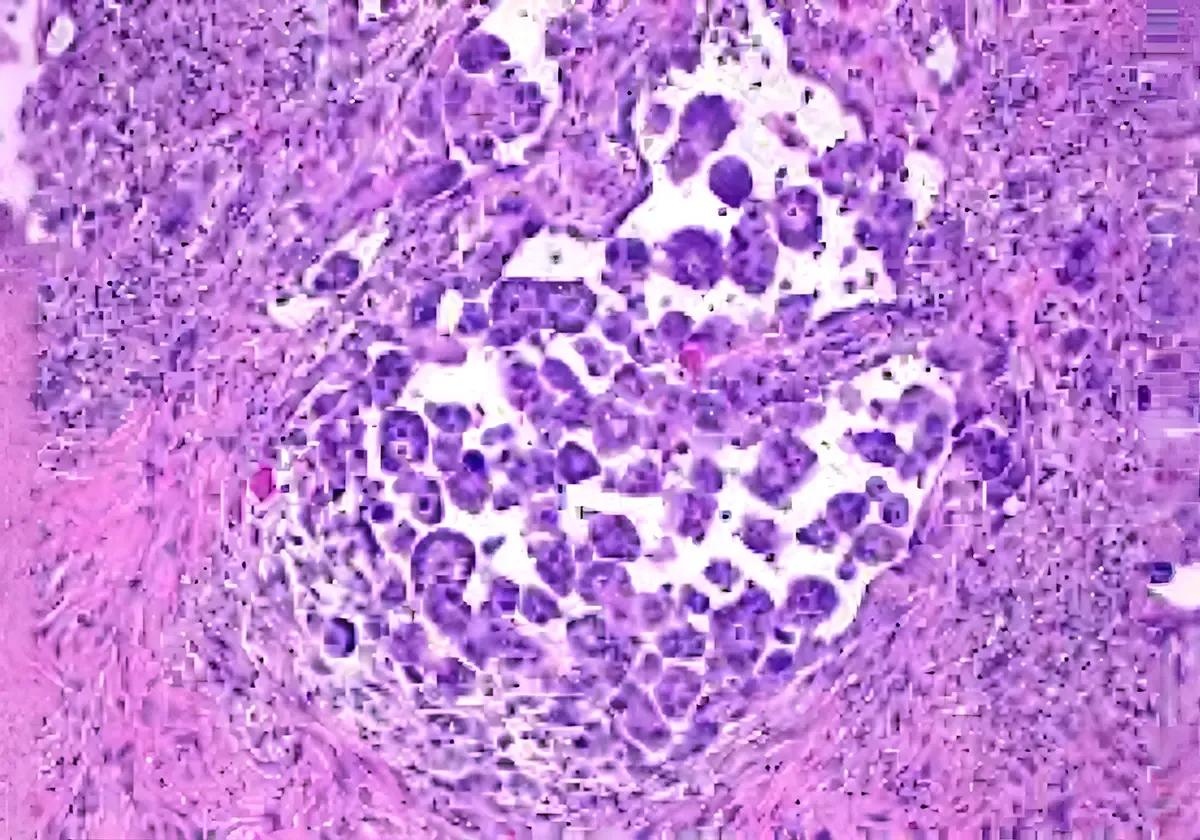

There are two subtypes of mesothelioma; epithelioid and sarcomatoid. A person can have one or both (biphasic or mixed) subtypes of mesothelioma. The subtype and location of mesothelioma affects the rate at which mesothelioma develops and the effectiveness of treatment.

Sometimes a diagnosis is not able to be made from the pleural fluid. In this case a cardiothoracic surgeon will perform a pleural biopsy where a sample is taken and examined under a microscope.